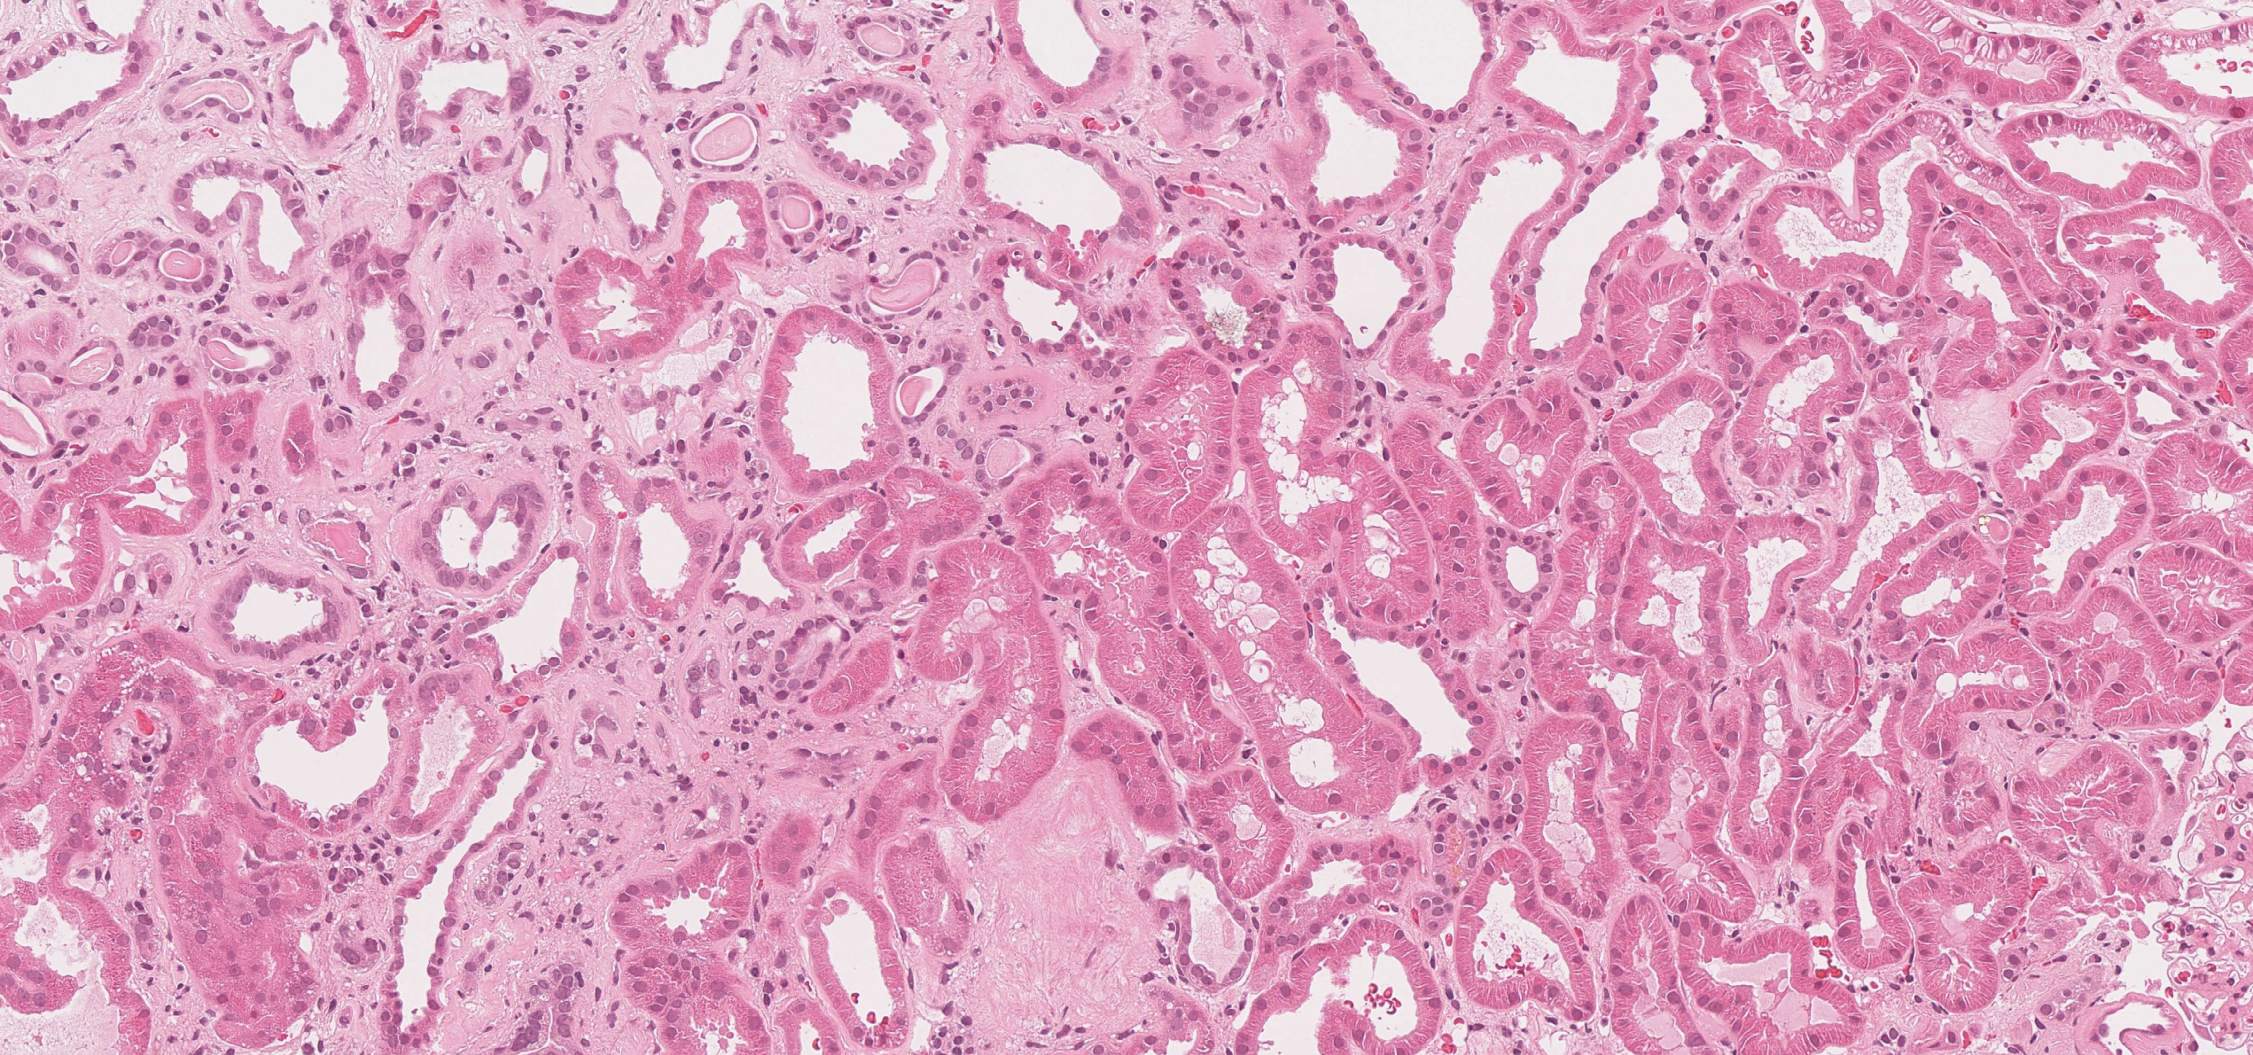

Kidney fibrosis is routinely evaluated by a rough estimate of the extend of fibrotic areas (slight,moderate, severe). This is difficult in routinely hematoxylin-eosin stained sections, because fibrosis is only weakly stained. The image below illustrates this: There is severe fibrosis in the left part and slight fibrosis in the right part.